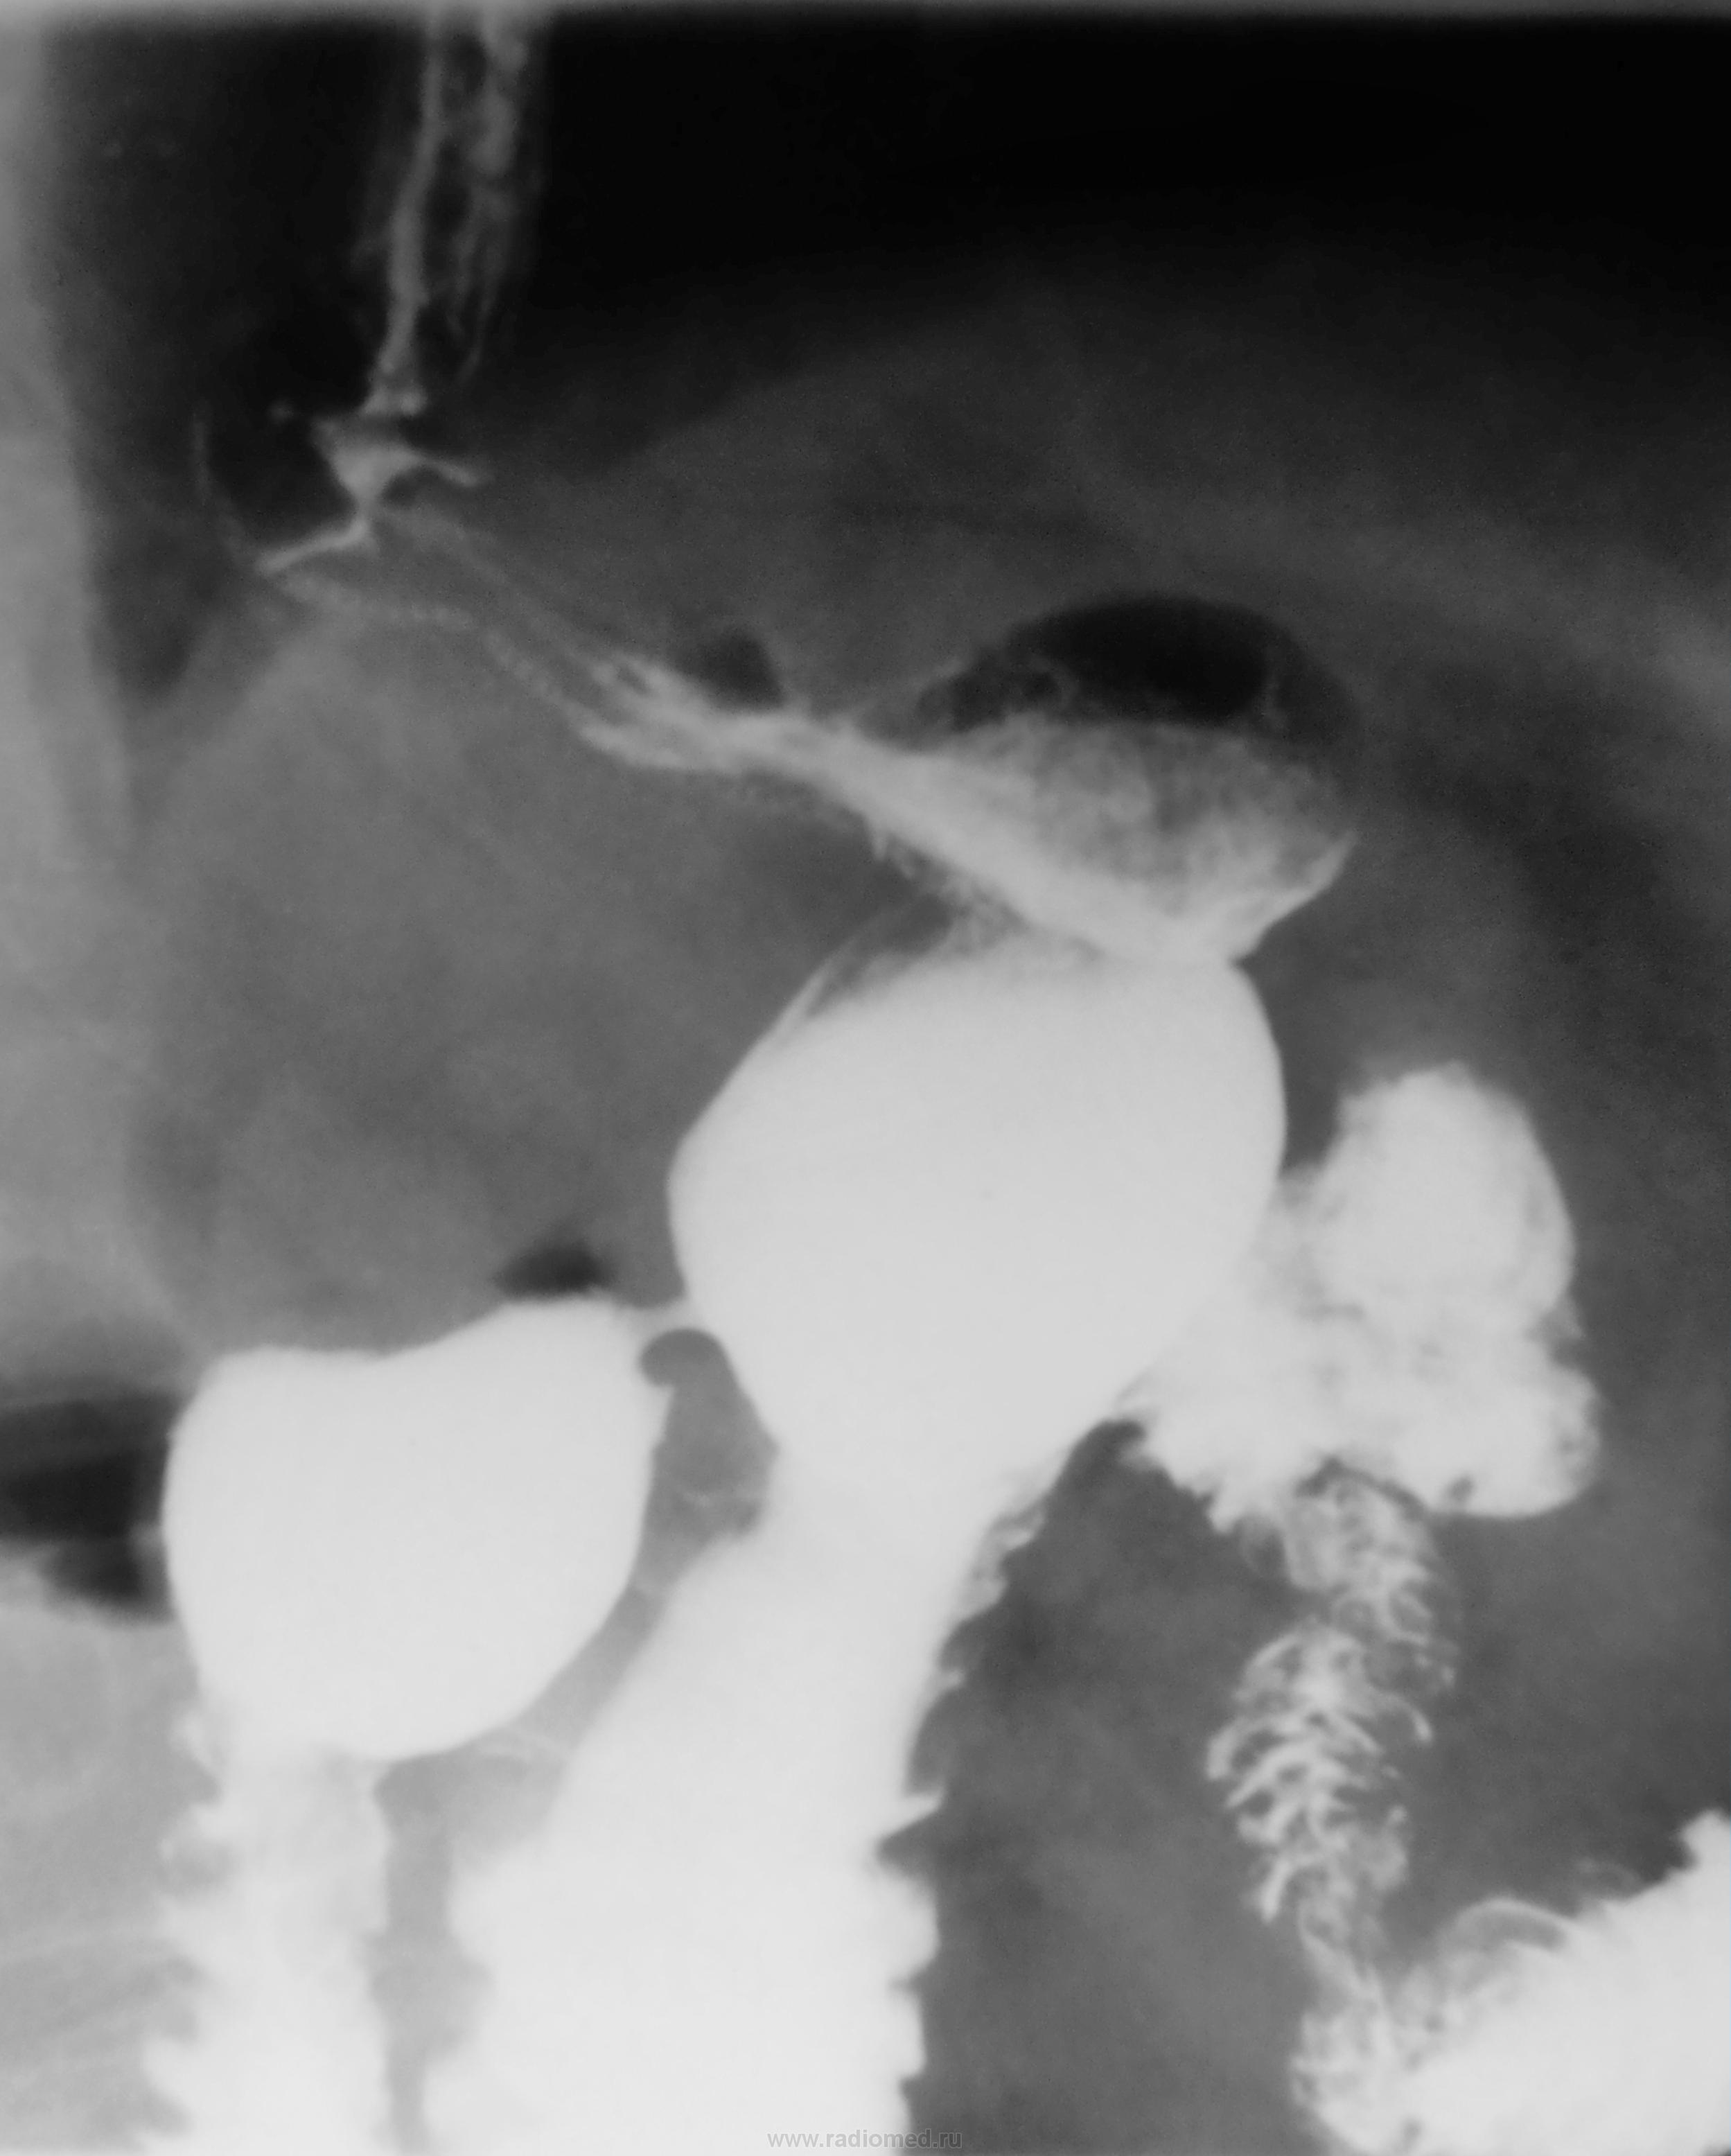

В настоящее время пациент утверждает, что пища не проходит. Лечащим врачом направлен на рентгенологическое исследование желудка.

По правой стенке пищевода определяется дефект наполнения, но после опорожнения пищеводной трубки вроде бы все становится ровным-сдавление органа из-вне? Чем? Пакетом лимфоузлов, конгломератом мягких тканей в результате тяжелого спаечного процесса? Или стеноз абдоминального отдела (если только не убирали верхнюю треть в области кардии и нижний отдел пищевода)?

В выделенном участке пищевода расширенные складки, наверное они потеряли эластичность. В проксимальном направлении расширение пищевода и ,вероятно, с нарушением паасажа. Привратник сужет, возможно функциональное.

Сужение диафрагмального отдела  с супрастенотическим расширением и некоторой "подрытостью" контура в наддипфрагмальном отделе пищевода: рецедив Cr? послеоперационный рубцовый стеноз? - биопсия!

А, может быть супрастенотическое расширение - это диафрагмальная грыжа?